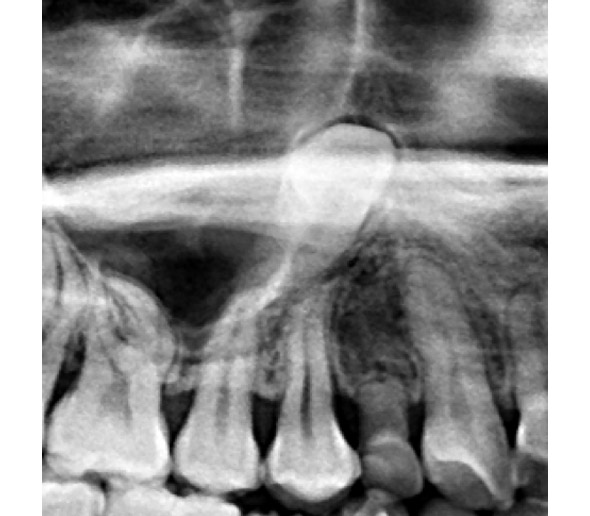

(兩條紅線中間黑色區域即為神經管)

外面拔完時常術後唇麻舌麻,本院發生趨近於零